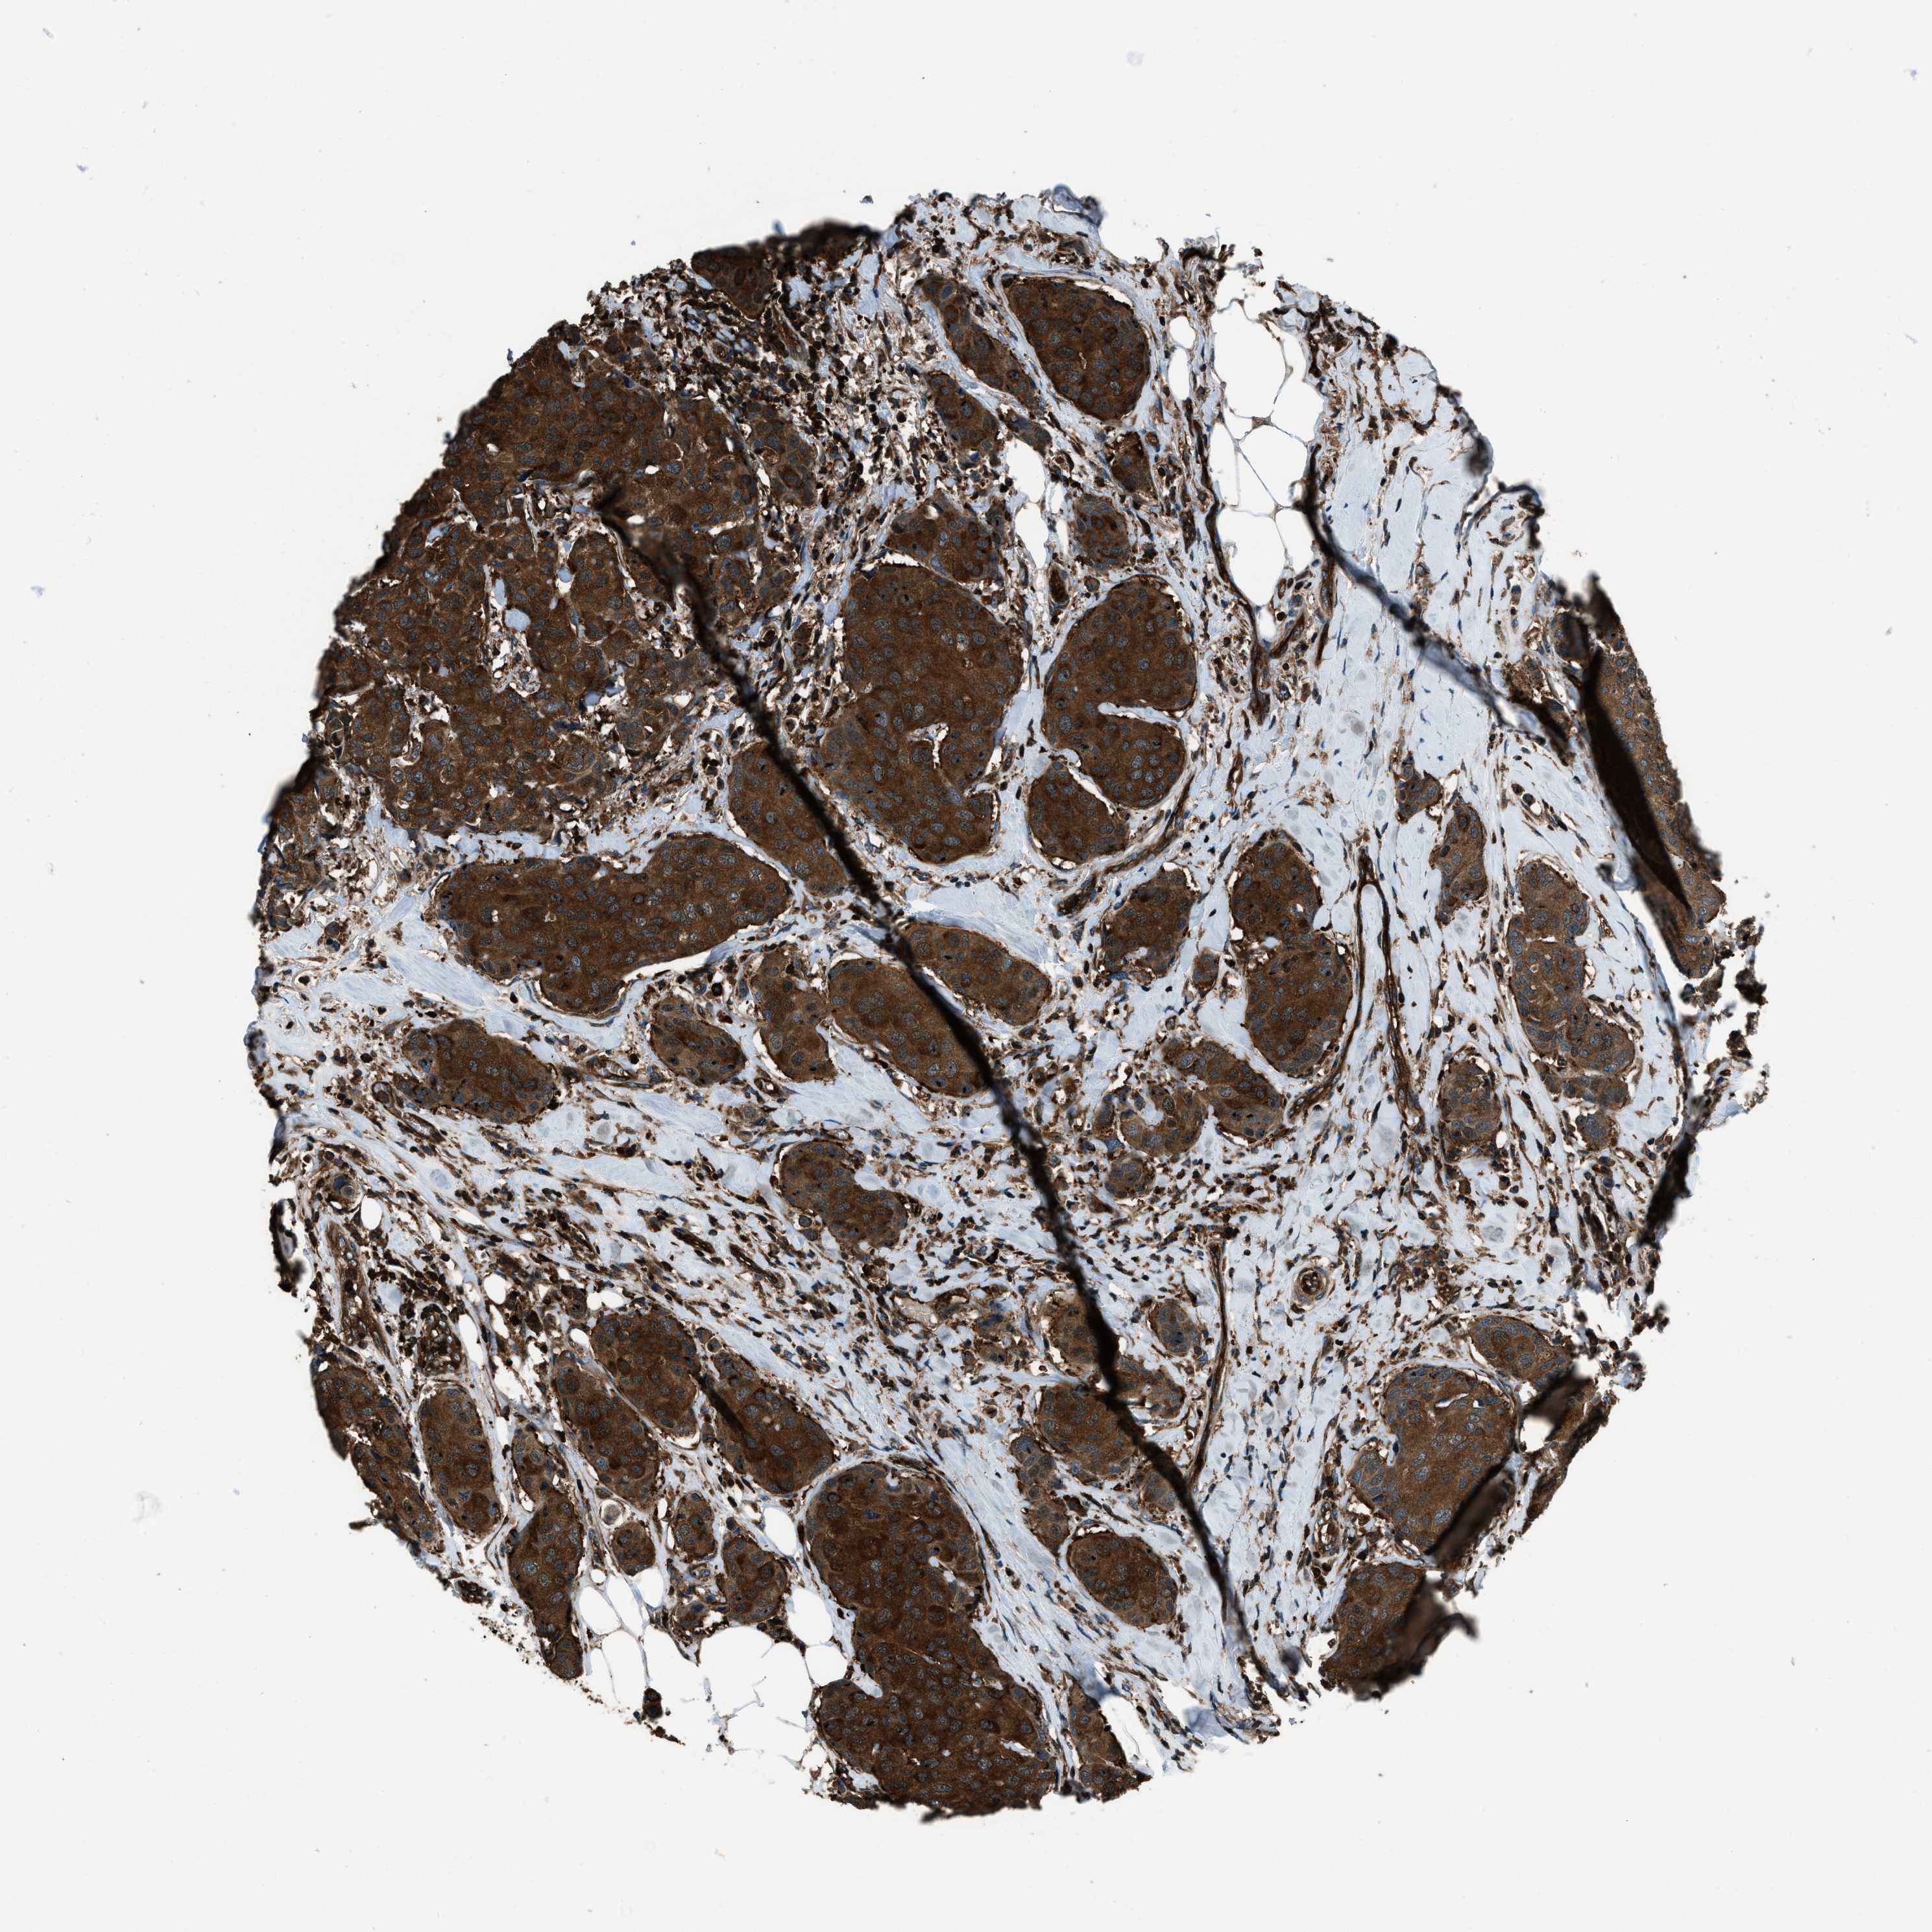

CANCER BREAST CANCER Show tissue menu

BRCA TCGA BRCA VALIDATION PROTEIN EXPRESSION